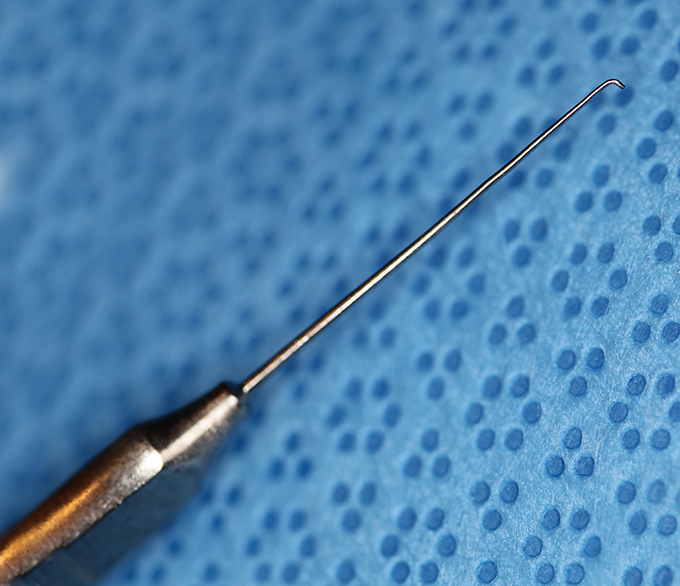

Hook, Sinskey

Sinsky

Catalog: Storz E545

Typical Use(s): Rotate IOL; Position haptics

Hook, Sinskey (Enlarged)

Sinsky

Catalog: Storz E545

Typical Use(s): Rotate IOL; Position haptics